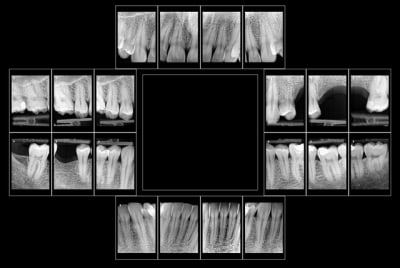

Patient 26 ans, à qui il manque 46, 25 et 26.

Pour l'instant je vous propose la partie préparation et mise en place de l'implant en 46, la suite peut être bientôt.

Dans l'ordre si le site veut bien, wax-up ( cirage pour céramik ;) ) , guide radio, et scan.

Photos pré-op, indicateur de direction en place et post-op.

Il s'agit d'un implant astra osseospeed de 5 mm de diamètre et 9 de long.

Prothèse prévue à 6 semaines.